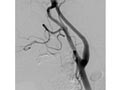

Angiogram of the Head and Neck

An angiogram of the head and neck is an X-ray test that uses a special dye and camera (fluoroscopy) to take pictures of the blood flow in the blood vessels of the head and neck. An angiogram of the neck (carotid angiogram) can be used to look at the large arteries in the neck that lead to the brain. An angiogram of the head (cerebral angiogram) can be used to look at the veins or the four arteries (four-vessel study) carrying blood to the brain.

During an angiogram, a thin, soft tube called a catheter is placed into a blood vessel in the groin or just above the elbow. The catheter is guided to the head and neck area. Then an iodine dye (contrast material) is injected into the vessel to make the area show clearly on the X-ray pictures. The angiogram pictures can be made into regular X-ray films or stored as digital pictures in a computer.

An angiogram can find a bulge in a blood vessel (aneurysm). It can also show narrowing or a blockage in a blood vessel that slows or stops blood flow. An abnormal pattern of blood vessels (arteriovenous [AV] malformation) or abnormal vessels near a tumor can be seen.